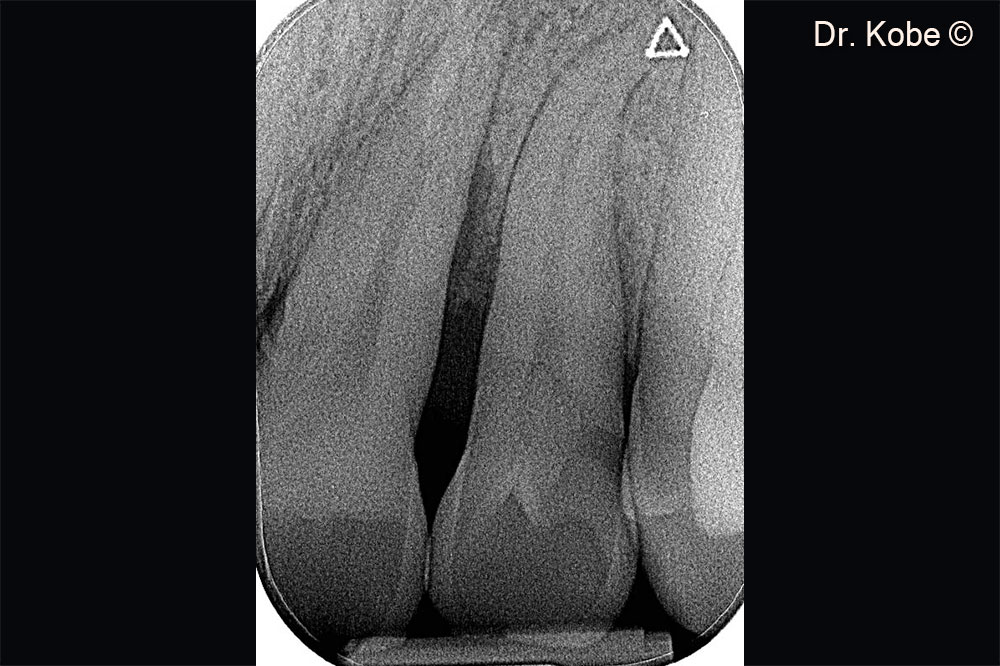

Vertical bone defect on the radiograph

Radiograph 1 year after treatment